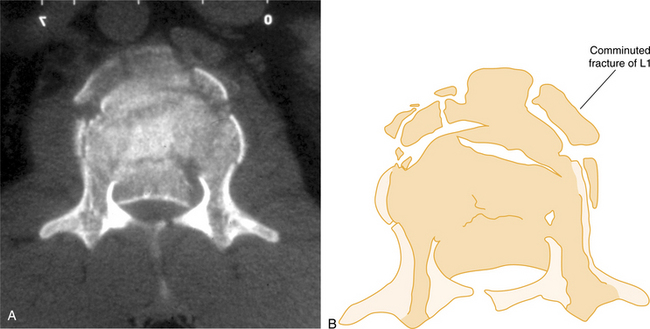

Vertebral compression fractures (VCFs) are the most common osteoporosis-related spinal fractures presenting with clinical symptoms of back pain, posture change, loss of height, functional impairment, disability, and diminished quality of life (Fig. 24-4). These can occur without injury or fall when the bone becomes so porous or weak and it begins to compress (see the section on Fractures in Chapter 27). By age 90 years, the force required to produce failure of the L3 vertebrae is approximately one-fourth the compressive failure force at age 30 years.55

Figure 24-4 Computed tomography of unstable comminuted vertebral compression (burst) fracture of the lumbar vertebra (L1). (From Marx JA: Rosen’s emergency medicine: concepts and clinical practice, ed 6, St Louis, 2006, Mosby.)